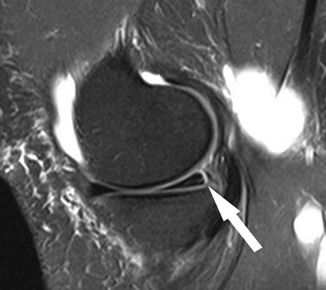

Hash等指出,Ramp损伤在MRI上的最突出 标志是在内侧半月板后角与后内侧关节囊之间插入了一个薄层的液体信号,观察内侧半月板后角与滑膜分离征象。

病例图片(均来自网络):